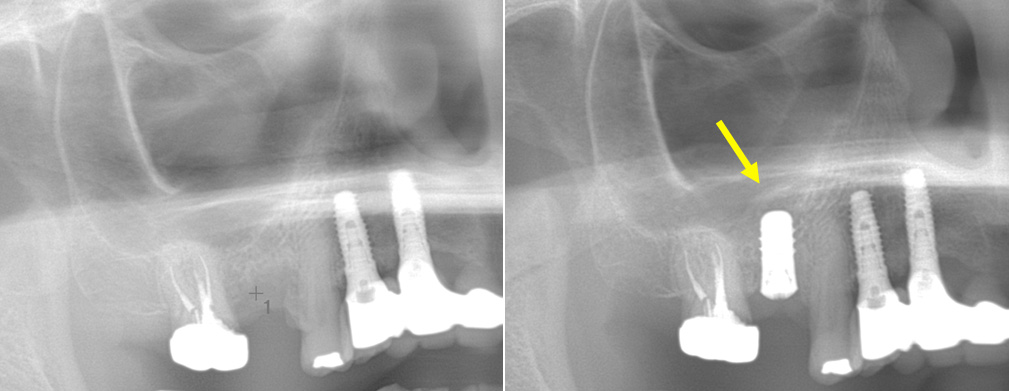

インプラント治療は外科処置を伴うためにリスクがあります。下顎の神経(下歯槽神経)を傷つけないように、上顎の骨の空洞(上顎洞)に突き抜けないように計画します。ゆえに、歯科医師は、最新の知識による十分な検査と確かな診断ができ、技術に熟練している必要があります。

インプラント埋入のために、上顎の奥歯の骨の厚みが足りない場合に骨を作る処置です。もともとの骨の厚みにより、ソケットリフトもしくはサイナスリフトを選択します。骨を作る程度により治療内容や期間はさまざまです。